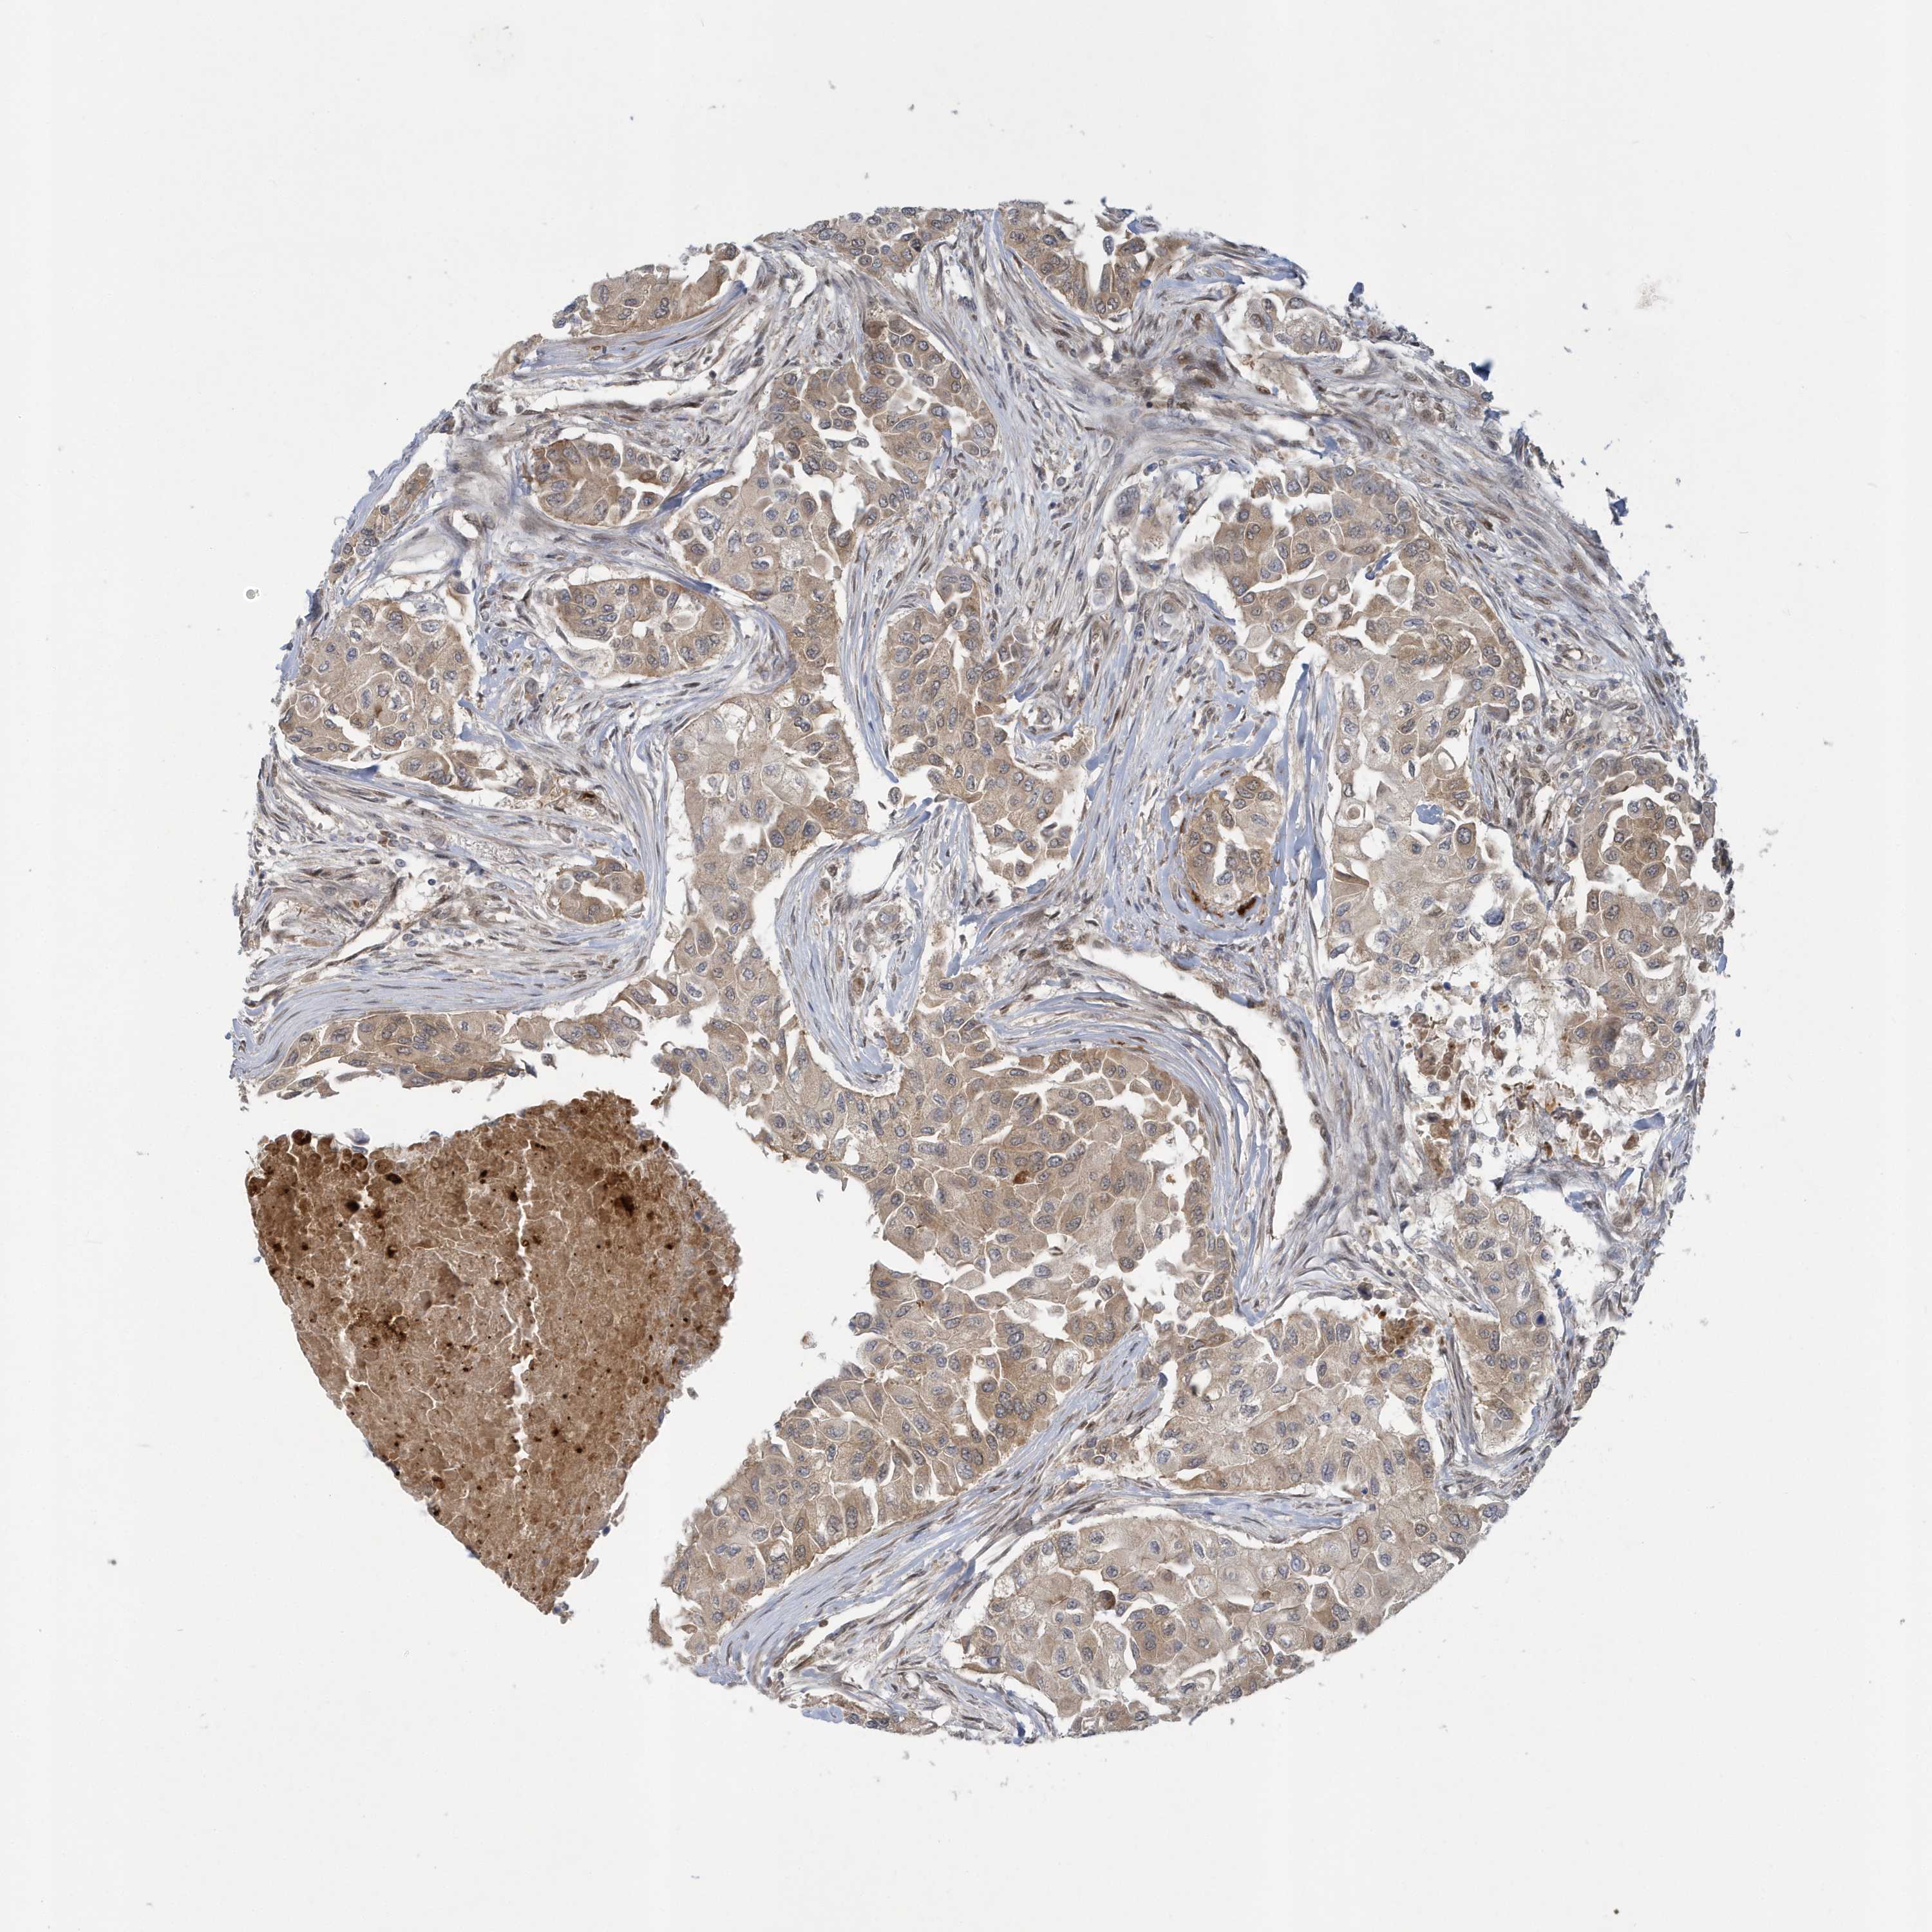

CANCER BREAST CANCER Show tissue menu

BRCA TCGA BRCA VALIDATION PROTEIN EXPRESSION